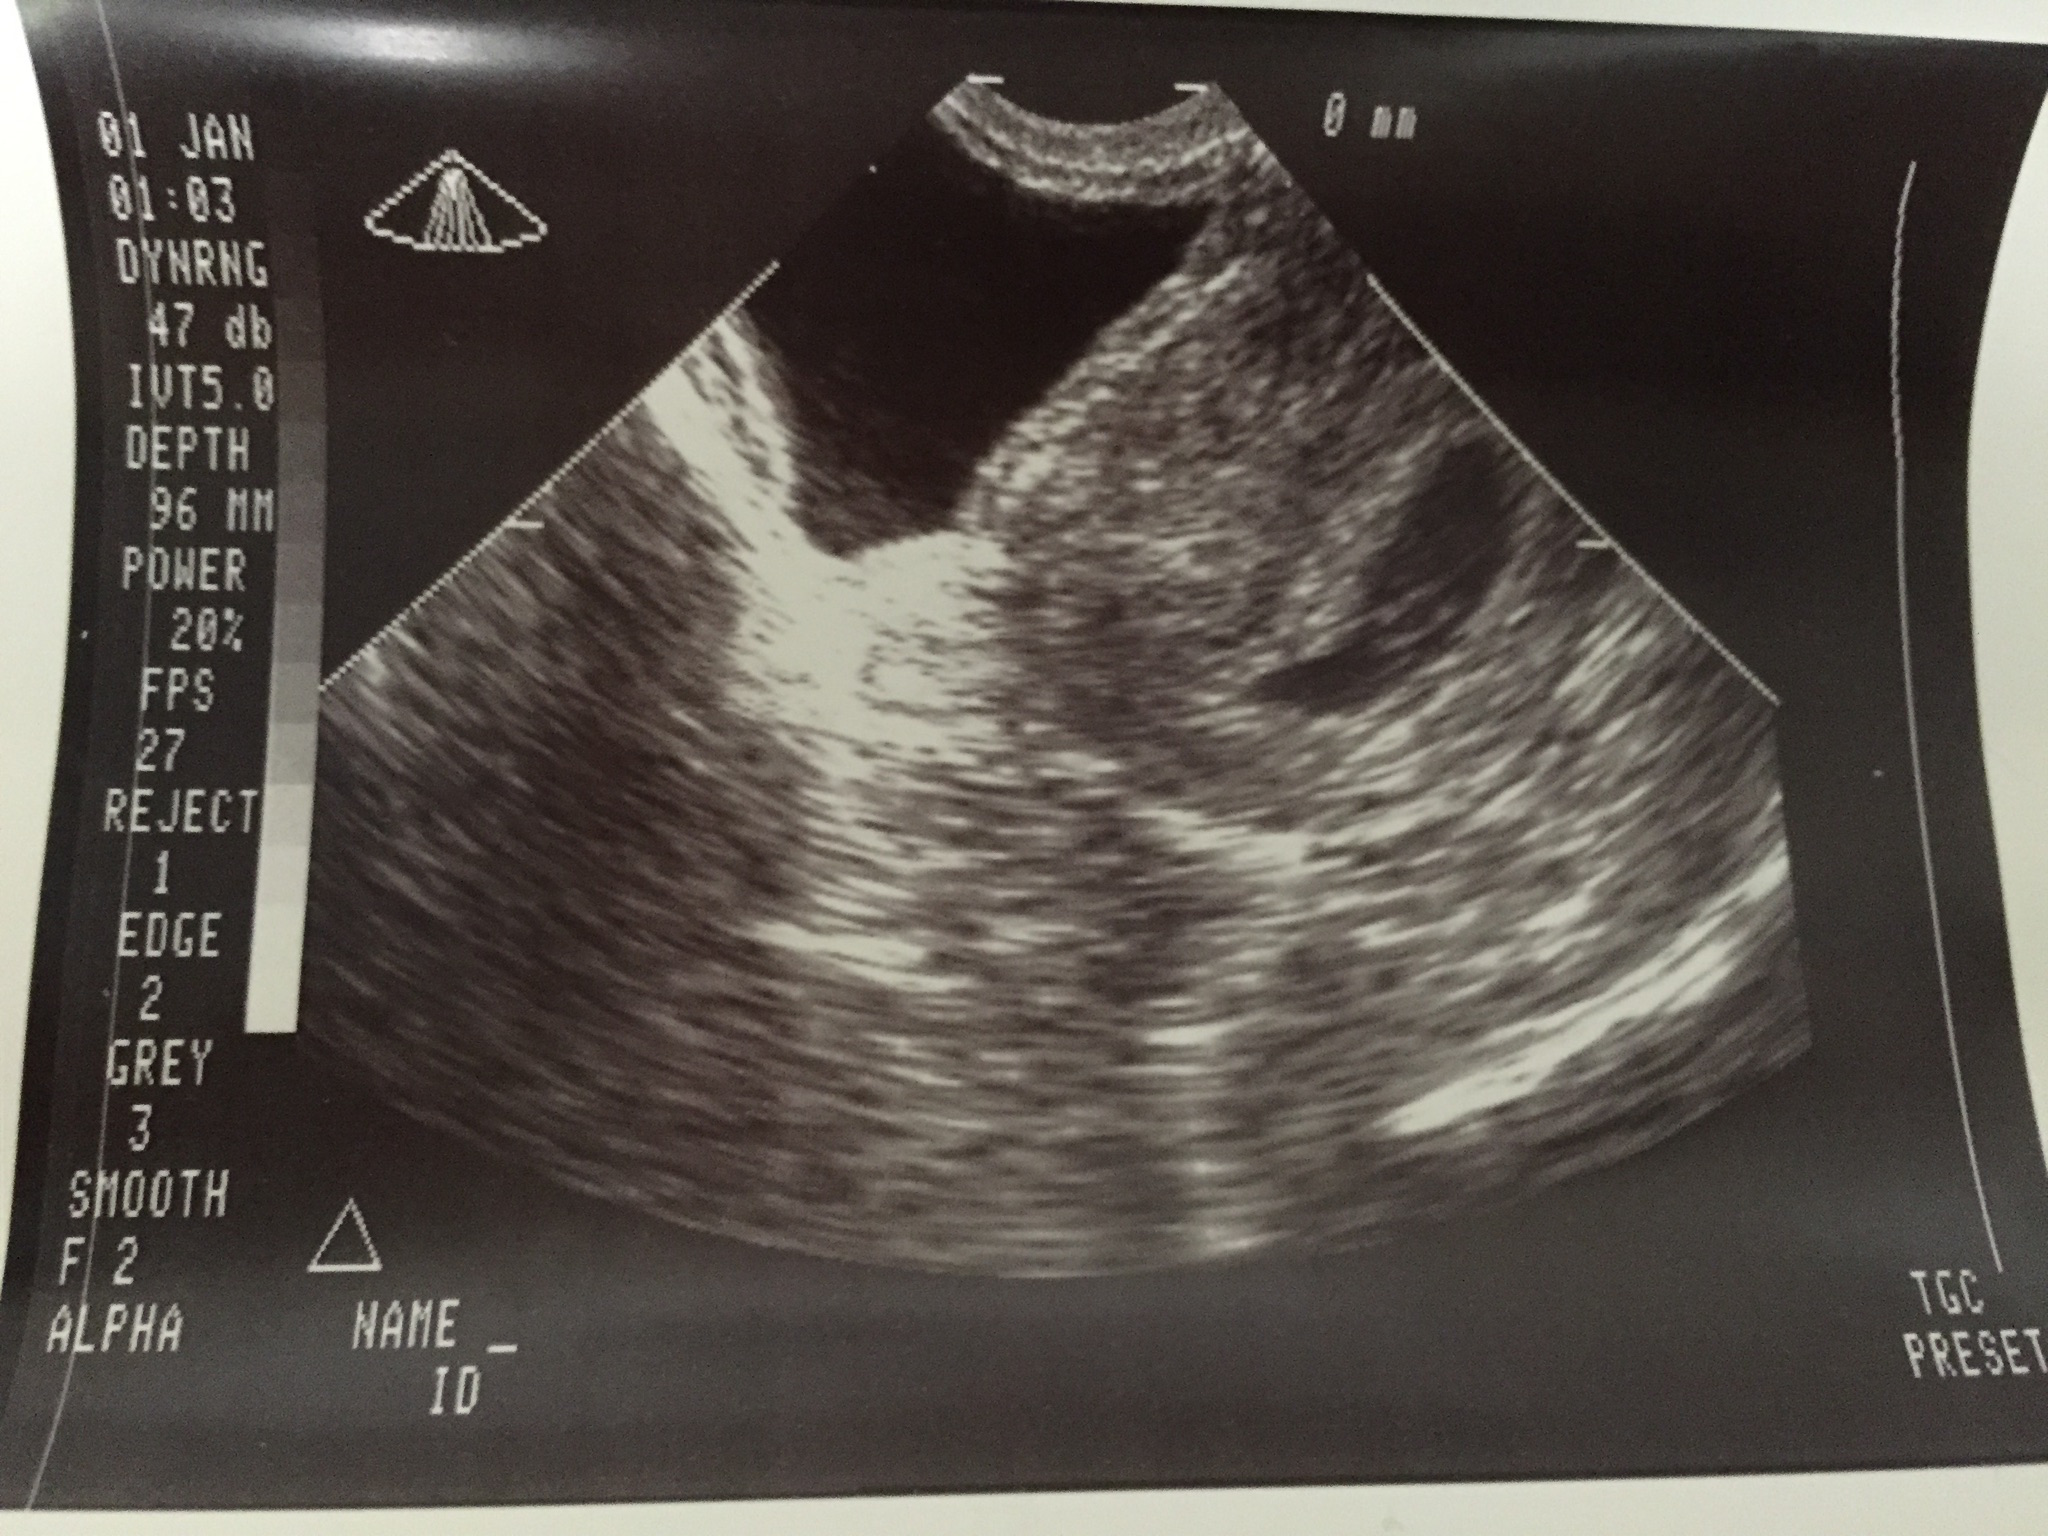

Hi everyone, I am not exactly sure what I am looking at as all the photos I compare my ultrasound to are a different shape and more centered... just a little confused. What are your thoughts on the Ramzi Prediction based on my us photo? This was a vaginal us done on 7w 2d. Thank you for any predictions or hep :)

Attachment 24412